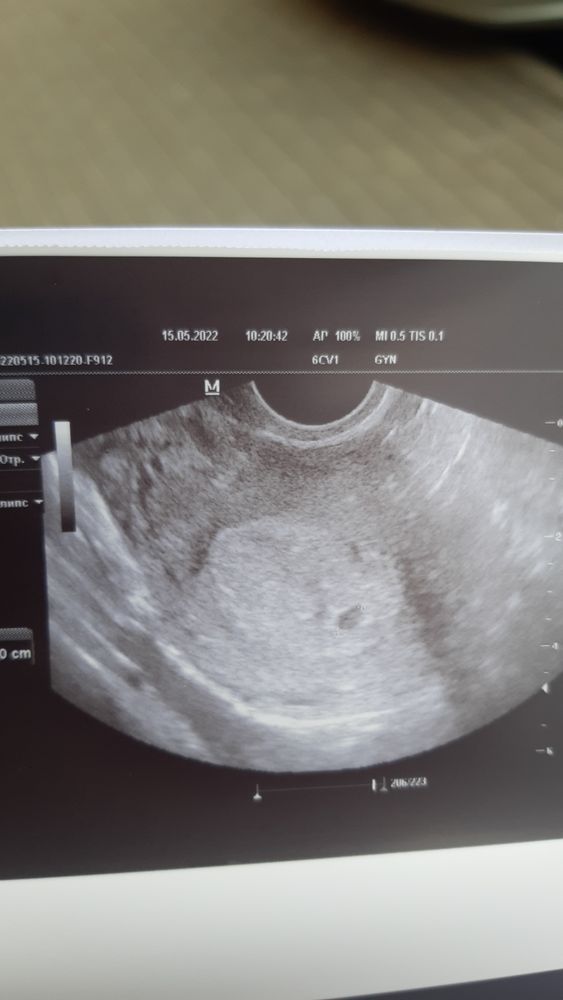

Узи на 20 дпо

Беременность- 1 триместр ( только до 10 недель)Девочки, кто был на узи на 20 (+/-) дпо, что на таком сроке удалось рассмотреть? Может у кого под рукой фото узи есть. Интересно как там все развивается, и когда лучше идти, что бы понять маточная ли беременность☺️☺️☺️

Была на 20 дпо, увидели только ПЯ 4 мм. Овуляция была поздней